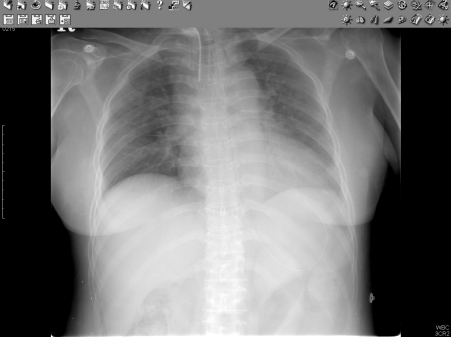

영상저장전송시스템 (Picture Archiving and Communication System, PACS)

디지털 상태로 의료영상을 획득, 저장, 전송하고 의료진들이 컴퓨 터를 이용해 이를 조회, 검색, 판독할 수 있도록 지원하는 포괄적인 디지털 영상관리 및 전송시스템

영상저장전송시스템(PACS)의 기대효과

- 소모성 비용(필름과 현상정착액) 및 인건비 절감

- 필름 보관을 위한 공간 및 관리 비용 절약

- 재촬영 감소로 인한 비용 절감, 환자의 불만 요인 감소

- 촬영 당일 진료 가능

- 의료 영상의 접근성 향상 (언제 어디서든지 조회 가능)

- 의료 영상의 질적 향상 및 신속 정확한 판독 가능

* DICOM (Digital Imaging and Communications in Medicine) : 의료용 기기에서 디지털 영상과 통신에 사용되는 표준